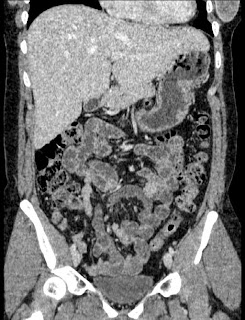

44 year old female with a long medical history. Undergone repeated surgeries for prox. 30 years. Not always fully understood what the purpose has been or expected outcome from all the procedures.

2009